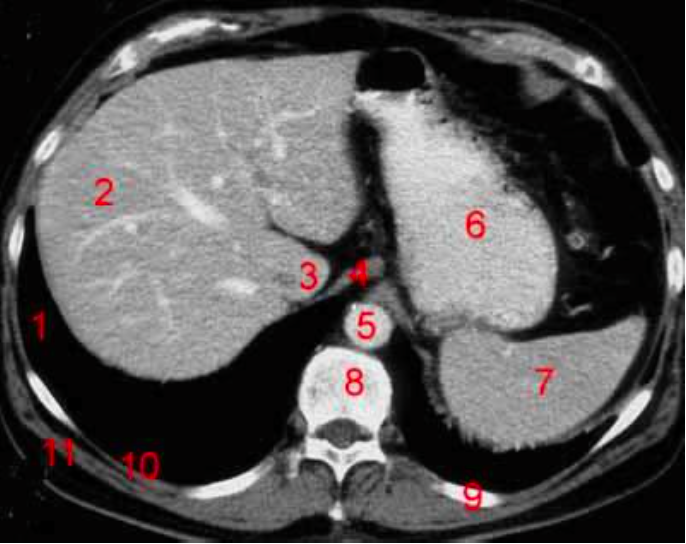

Number 2?

Rt lobe of liver

Number 4?

Head of pancreas

IVC

Rt lobe liver

Number 8?

Body of thoracic vertebra

Number 10?

Rt rib